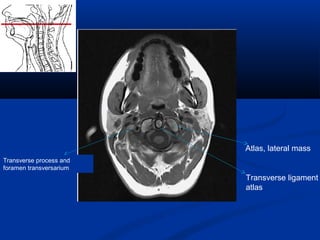

Atlas, lateral mass

Transverse ligament

atlas

Transverse process and

foramen transversarium

Atlas, lateral mass Transverseligament atlas Transverse process and foramen transversarium